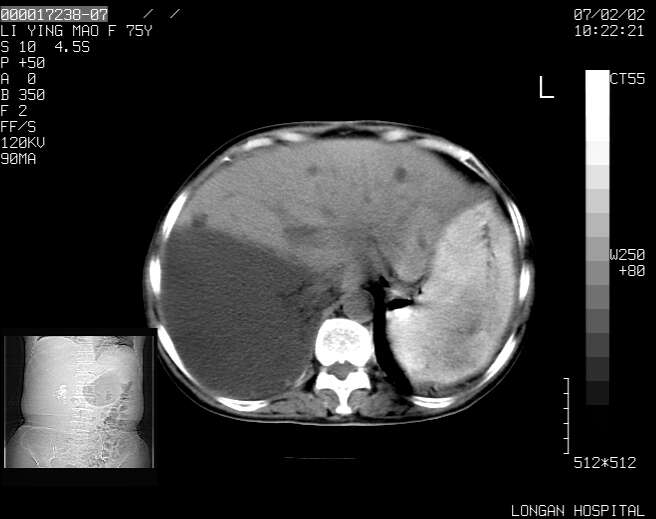

以下是引用dyqct在2007-2-10 8:53:00的发言:[br]考虑:1、肝脏多发囊肿[br] 2、左肾囊肿,右肾多发结石并积水。[br] 3、右胸少量积液。[br] 4、右肾周包裹性积液或淋巴管瘤(有见缝就钻的征象、薄隔、小结节状钙化)?[br] 5、腰椎动脉瘤样骨囊肿?[br] [br] [br]